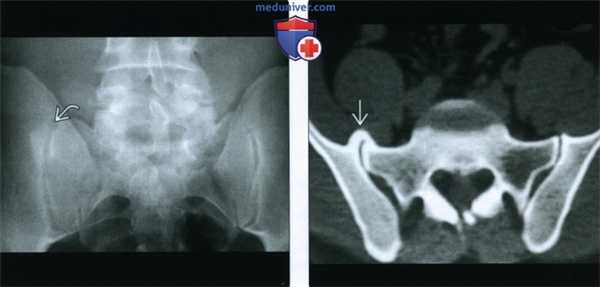

(Слева) Рентгенография в ПЗ проекции: признаки умеренно выраженного ОА локтевого сустава, включая остеофиты и гипертрофию костной ткани в области бугристости лучевой кости. Оссификат, покрытый кортикальным слоем в проксимальном сухожилии разгибателя, соотносится с хронической тендинопатией, либо предшествующим повреждением.

(Справа) КТ, сагиттальная проекция, без контрастного усиления: хронический ОА локтевого сустава с субхондральными кистами, остеофитами и сужением суставного пространства. Распространение костных патологических изменений иногда лучше визуализируется при КТ, чем при рентгенографии.

• Крестцово-подвздошные суставы: как правило, два признака:

о Склероз по ходу кортикального слоя синовиальной части сустава

- Отсутствие эрозий или анкилоза

о Краевые остеофиты:

- Либо у основания крестцово-подвздошного сустава, либо у места переходя синовиальной части в несиновиальную (от 1/2 до 1/3 расстояния от вершины крестцово-подвздошного сустава)

- Визуализируется в качестве округлого уплотнения; иногда ошибочно расценивается в качестве костного островка или метастаза

4. КТ при остеоартрозе осевого скелета:

• Хорошо визуализируется гипертрофия кости во всех вышеописанных отделах

• Краевые остеофиты крестцово-подвздошного сустава: хорошо визуализируется переднее перекрытие

(Слева) Рентгенография в ПЗ проекции: склеротическое «повреждение» на уровне верхней части правого крестцово-подвздошного сустава. Важно помнить, что ОА крестцово-подвздошных суставов может проявляться либо диффузным склерозом кортикального слоя, либо в виде округлых участков склероза в верхней или нижней части синовиальной порции сустава.

(Справа) КТ, аксиальная проекция, костный режим: у этого же пациента подтверждается наличие очага склероза, представленного типичным краевым остеофитом, перекрывающим крестцово-подвздошный сустав.